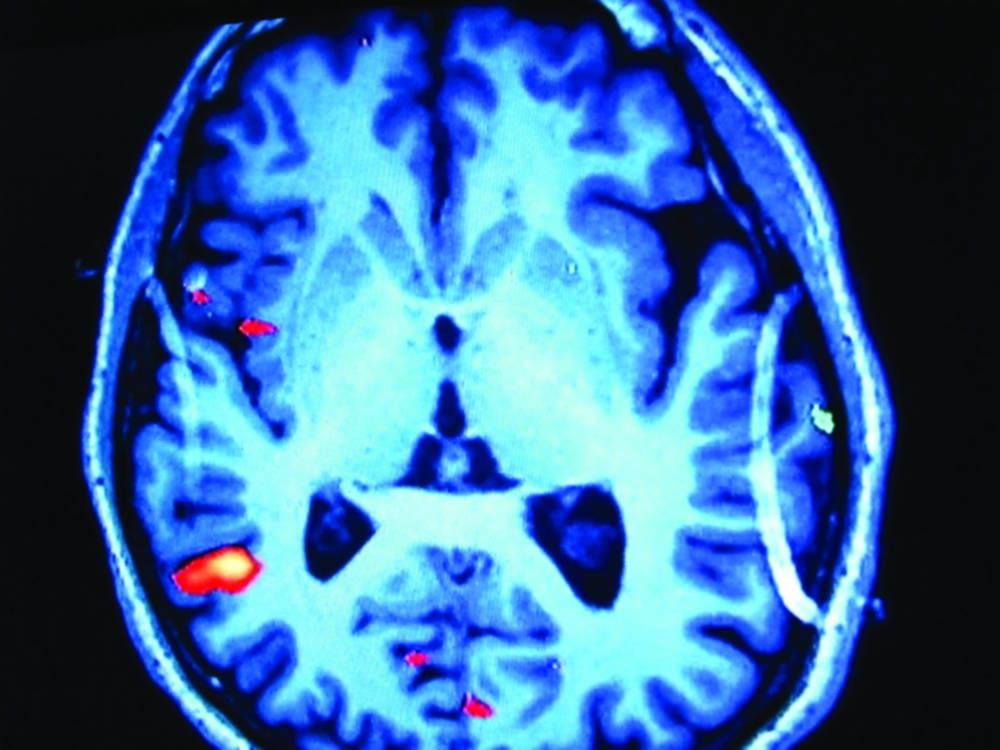

Schizophrenia could be caused by abnormal levels of neurotransmitters dopamine and glutamate, according to new research carried out at Imperial College London.

Researchers found evidence that glutamate-releasing cells in the hippocampus influence the activity of dopamine-releasing cells, which in turn are linked with causing psychosis.

The Medical Research Council funded the research and the team scanned the brains of 16 people at-risk for psychosis and 12 healthy volunteers, to measure levels of dopamine and glutamate.

A correlation was found between the glutamate levels in the hippocampus and the dopamine levels in the brain.

This is strong evidence that there could be a link between glutamate and psychosis in many patients.